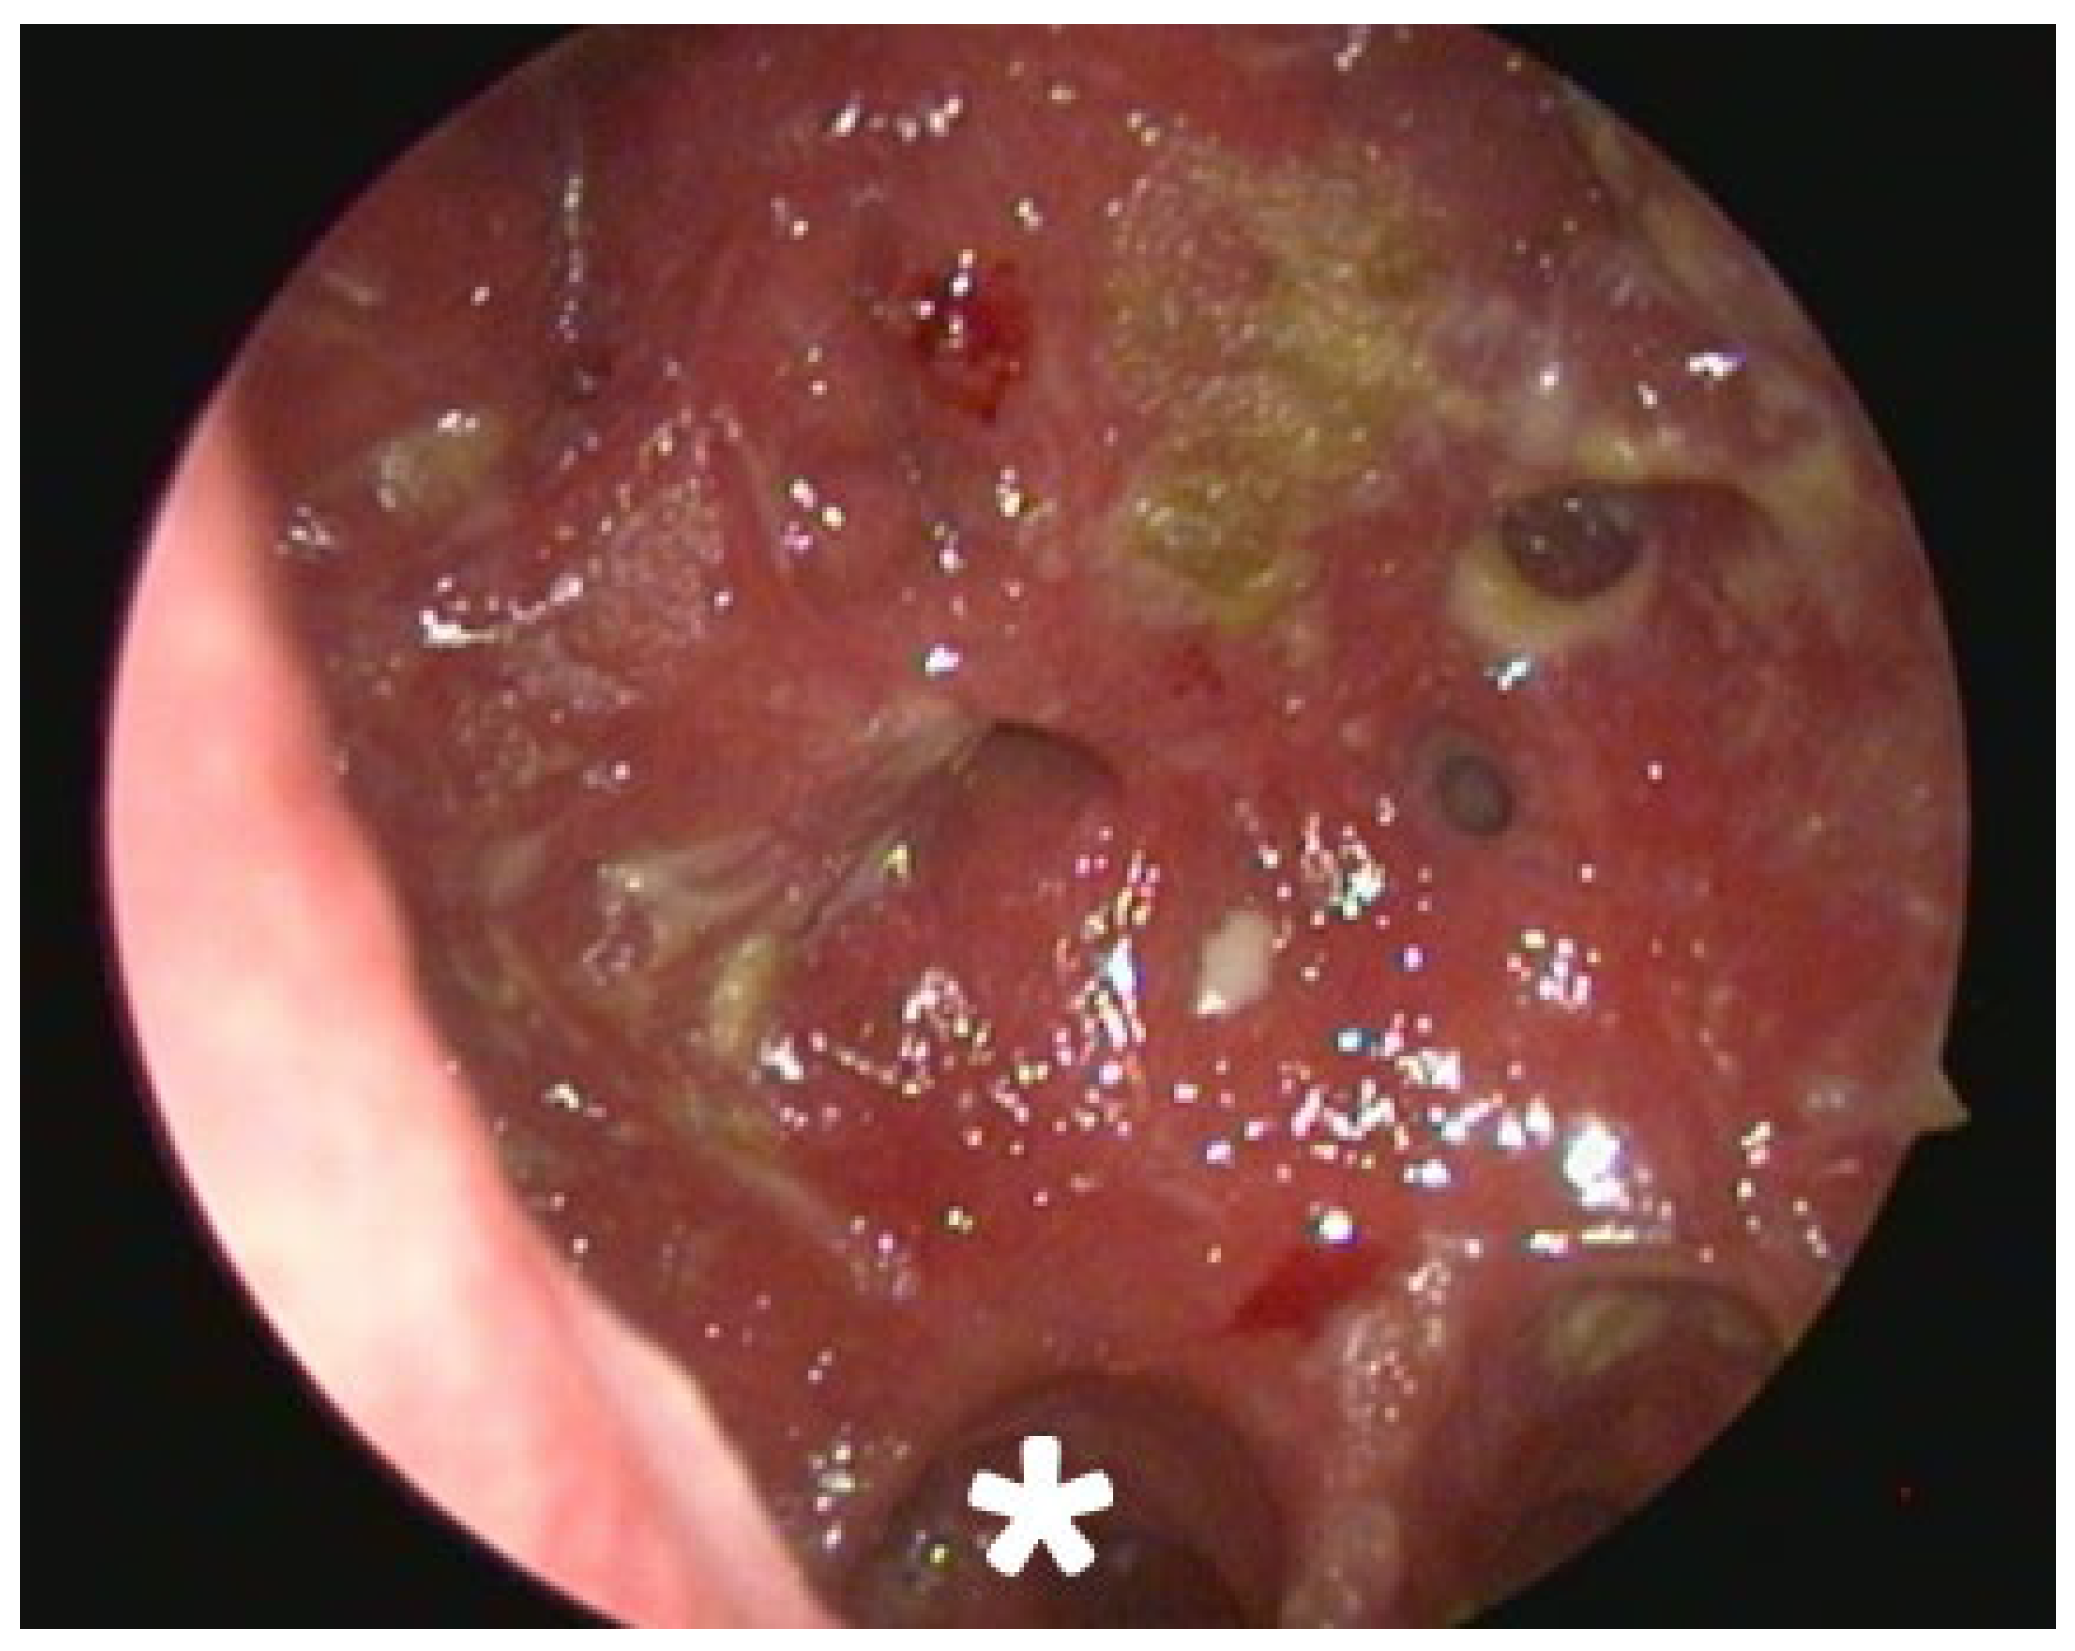

2.2. Clinical and Radiological Findings (2024)

| 2024 | Secondary atrophic rhinitis | Endoscopy, CT scan. Treatment initiation. 3-month follow-up. |